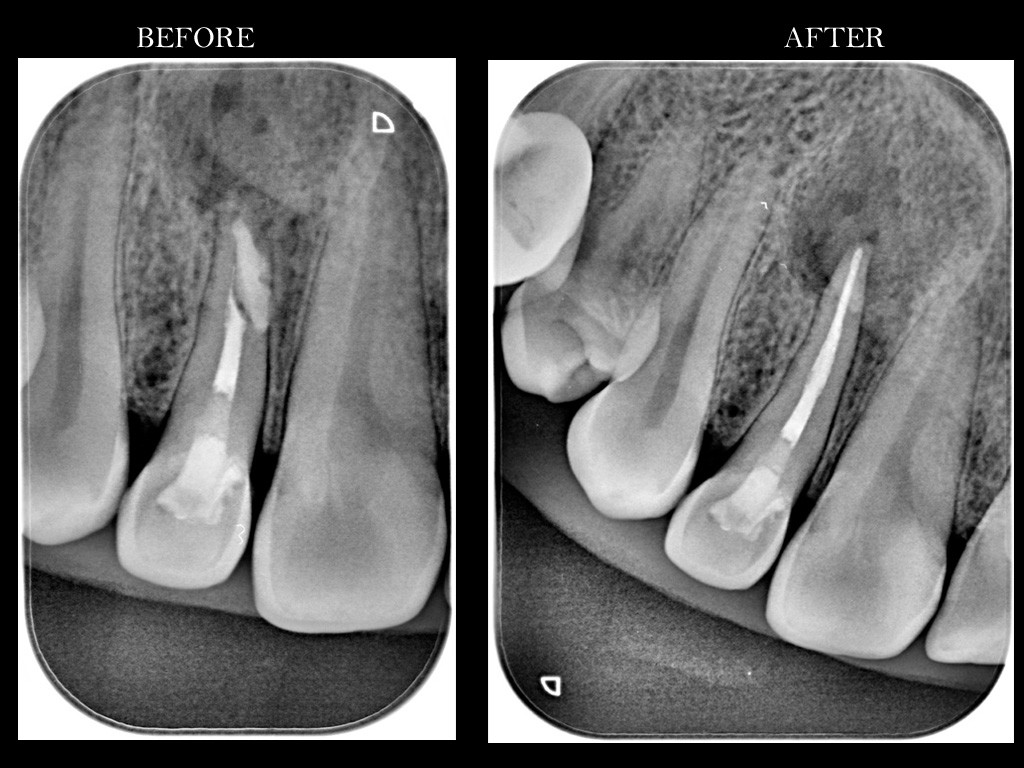

Περιστατικά